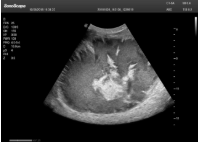

1單晶體凸陣探頭

采用了單晶體探頭材料,探頭面是凸面,接觸面小,成像視野呈扇形,應用廣泛,常應用于腹部、婦產、肺部等相對部位較深的臟器。

肝癌